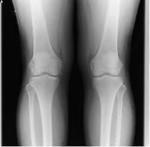

先ずは、整形外科での検査/診断受診をお勧めします。

レントゲン検査で骨の異常を確認をして下さい。

スポーツ選手、高齢者などは骨や軟骨などのヒビ、骨折、損傷などの疑いがあります。